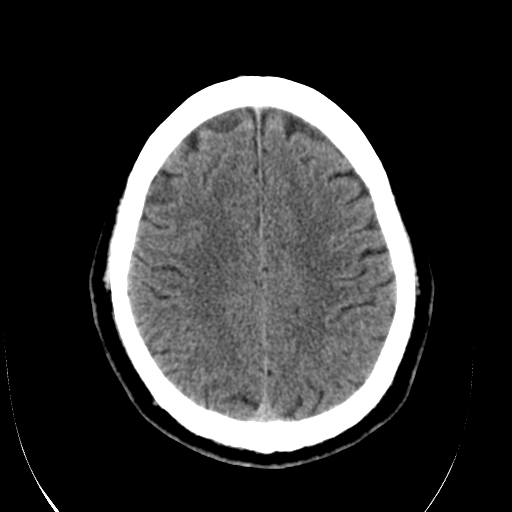

标题: CT28335:男,58岁,请各位看看是不是有脑积水,蝶窦内高密 [打印本页]

标题: CT28335:男,58岁,请各位看看是不是有脑积水,蝶窦内高密

轻度积水,蝶窦正常。

脑积水!建议行mri!

1)脑积水。2)副鼻窦炎。